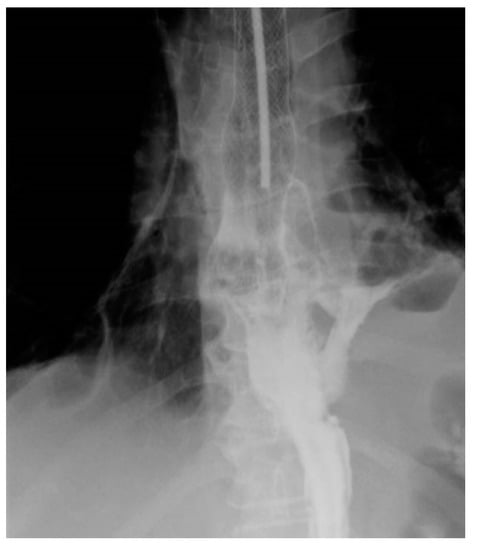

Persistence of the fistula after the placement of the stent, radiologically demonstrated, requires repeating the endoscopy and repositioning or replacement of the stent or the insertion of another stent (Figure 1 and Figure 2).

Figure 1.

Persistence of the fistula after stent placement—Type 2, due to reflux of the substance at the level of the distal end.